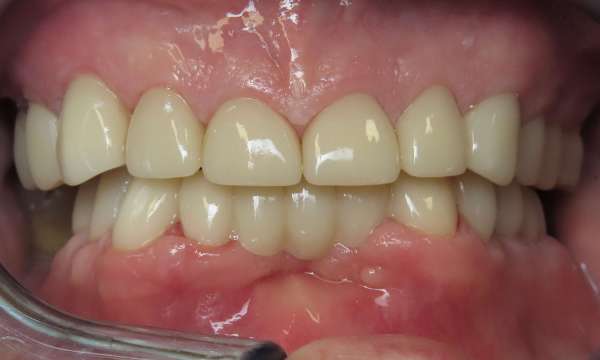

Full Mouth Restoration

This patient had severely worn most of his teeth from many years of clenching and destructive tooth grinding.  We were able to take him from his consultation, to a discussion of his options, to a final result of single crowns on most teeth with a bridge in the lower front.  We were so happy to deliver this result, improving his confidence, function, and quality of life.